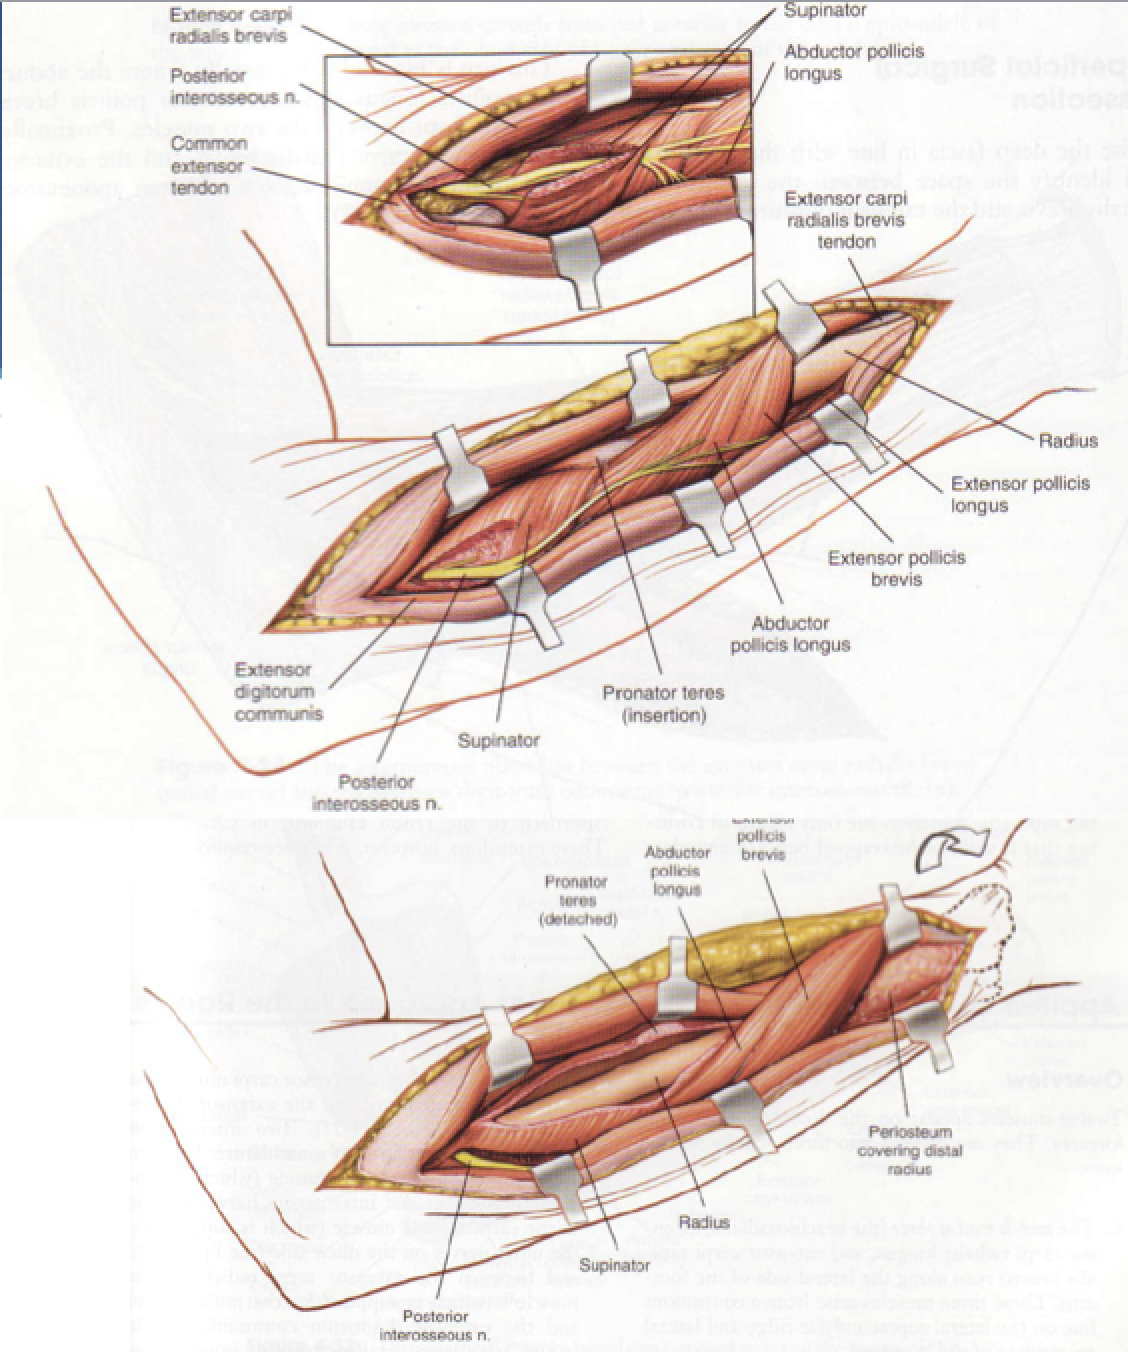

Thompson Approach Dorsal Forearm

Interval:

- Superficial: EDC (PIN), ECRL/ECRB (Radial n., PIN)

- Deep: Supinator (PIN) and Pronator Teres (median n.)

Approach: Distal extent of Kaplan at the elbow. Need to indenfity, expose and protect PIN as it leaves supinator and all of its branches. Retract posteriorly. Develop between Supinator and PT proximally.

Dangers: